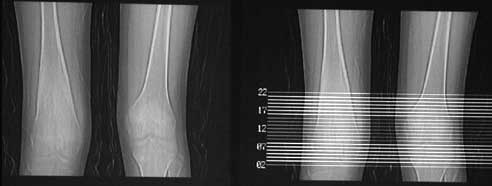

CT00198:股骨病变

男性,15岁,右下肢疼3年,加重1月无发热,局部无红肿.

瘤巢为低密度环,核为中心高密度灶。骨样骨瘤。典型,学习了。

右股骨下端骨样骨瘤。

典型骨样骨瘤。

较为典型的骨样骨瘤。